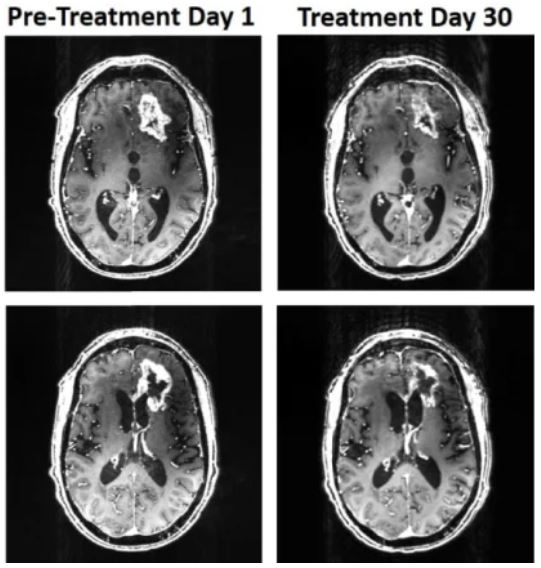

Ето колко много се е смалил туморът. Източник: Baskin et al., Front. Oncol., 2021

Цялото лечение продължава 36 дни. За този период глиобластомът се е смалил с цели 31 процента, казват изследователите. Според хората, които са се грижили за мъжа, неговата реч и когнитивни функции са се подобрили значително.